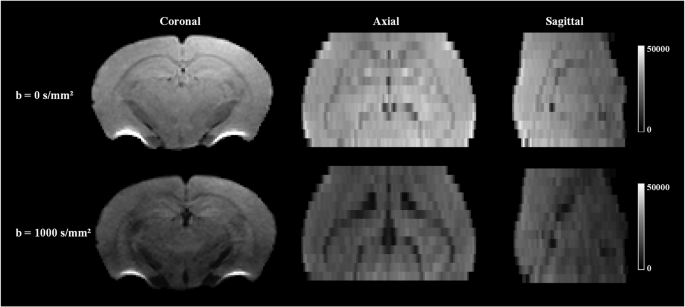

To provide a more comprehensive assessment of data quality, we present preprocessed relaxation-regressed dMRI images at TE = 22 ms from three orthogonal views: coronal, axial, and sagittal (Fig. 4). The inclusion of both in-plane and through-plane perspectives allows for the evaluation of intra-slice image quality and the consistency across slices, which is critical for ensuring the continuity of anatomical structures in the dataset. Additionally, we provide a representative example of MD, FA, NDI, and ODI images per age group (2, 6, 12, 18, and 24 months) in Fig. 5. This enables a direct comparison of data quality across different developmental stages, with all images showing approximately the same anatomical location.

Fig. 4 -